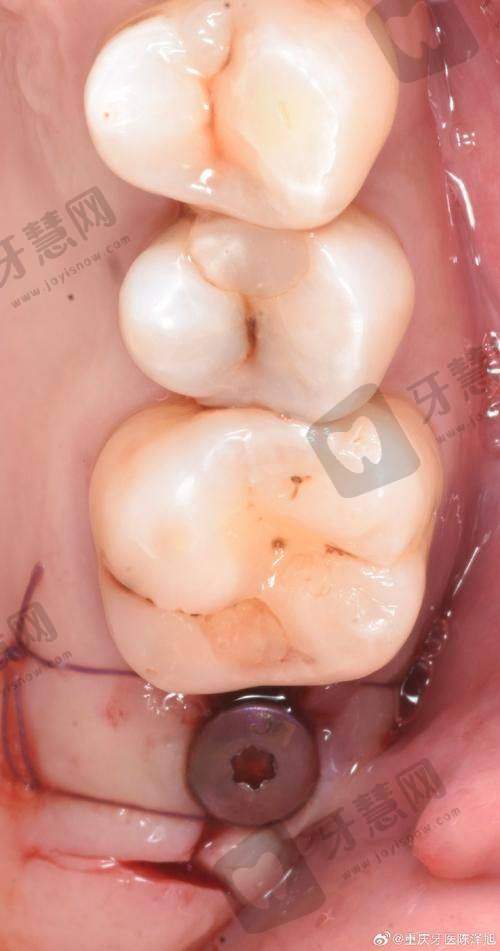

有一位患者牙齿状况较差,存在重度的牙周病,同时伴有牙齿缺失,希望进行种植牙手术。王菁医生先为患者进行了全方面的牙周系统治疗,通过龈下刮治、根面平整等方法改善患者的牙周健康状况。待牙周情况稳定后,为患者制定了穿颧骨种植牙方案。手术过程顺利,术后种植体稳定性良好。在修复期间,王菁医生还对患者进行了种植体的牙周维护,患者的牙齿功能和美观都得到了极大改善,对治疗成效非常满意。